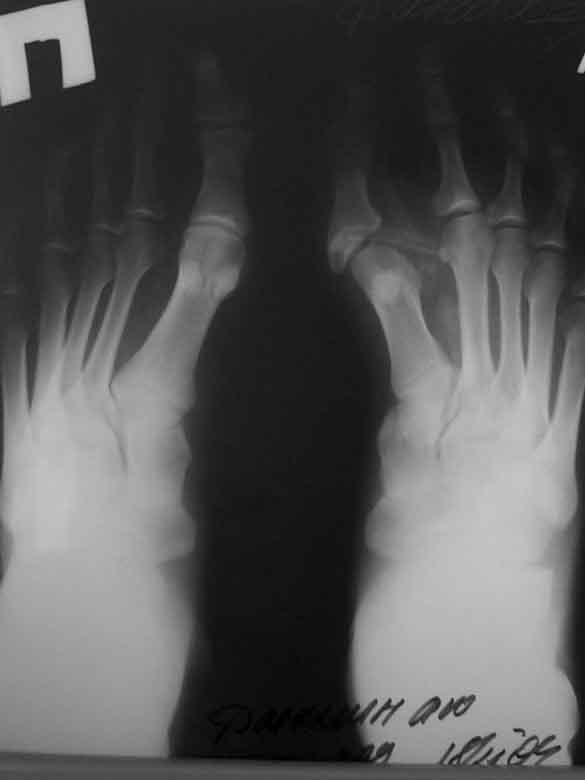

Больной Д. 28 лет, обратился с жалобами на боли и на наличие свища по подошвенной поверхности 1 п левой стопы. Жалобы беспокоят 1,5 года. Лечился амбулаторно проводились пункции откачивали гной (со слов больного).

Укорочение 1 п. Смещение о/ф 1 п кнаружи и к тылу. Пассивные активные движения 1 п в полномобъеме. На рентгенограмме определяется аномальная кость.

Происхождение такого состояния можно теоретически объяснить либо врожденной аномалией оссификации проксимальной фаланги большого пальца (два ядра)-об этом признаться я не слышал и не приходилось встречать в литературе, либо (что выглядит наиболее практичным) - это травма зоны роста в детстве по типу Salter-Harris 1 или 2 типа, что и привело к нарушению нормального роста первого пальца и деформации 1 плюсне-фалангового сустава. Не думаю, что пункциями и АБ можно вылечить сформировавшийся свищ, скорее более успешной тактикой в такой ситуации будет хирургическое иссечение свищевого хода после предварительного введения метиленой синьки. (все прокрашенные ткани иссекаются).

1. Судя по снимкам, рентгенограммам и клинике - это хр.остеомиелит ( и хр.артрит) одной из сочленяющихся костей 1ПФС, (я бы уточнил источник), свищевая форма, на фоне аномального развития 1 ПФС (врожденного или приобретенного - сейчас это уже не важно).